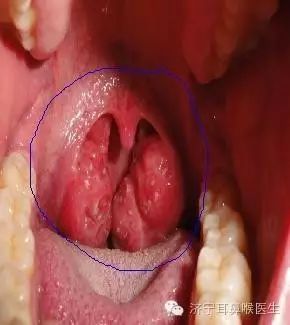

我们先来认识一下扁桃体。我们平时说的扁桃体,全名叫“腭扁桃体”,位于口咽两侧腭舌弓与腭咽弓围成的三角形扁桃体窝内,是咽淋巴组织中最大者。3-5岁时淋巴组织增生,腭扁桃体可呈生理性肥大,中年后逐渐萎缩。

慢性扁桃体炎定义为扁桃体的持续感染性炎症,通常发生在大龄儿童和年轻人,多由于急性扁桃体炎反复发作或因腭扁桃体隐窝引流不畅,隐窝内细菌、病毒滋生感染而演变为慢性炎症,是临床上最常见的疾病之一。慢性扁桃体炎可分为:增生型、纤维型、隐窝型。

慢性扁桃体炎常有急性扁桃体炎反复发作的病史。发作时咽痛明显,发作间隙可以有咽干、发痒、异物感、刺激性咳嗽等轻微症状,也可能出现口臭。有些患者,尤其小儿患者,由于扁桃体过度肥大,可出现睡眠打鼾、呼吸不畅、吞咽或言语障碍。扁桃体隐窝内的脓栓被咽下,刺激胃肠道,毒素被吸收,还可以出现消化不良或头痛、乏力、低热等全身反应。